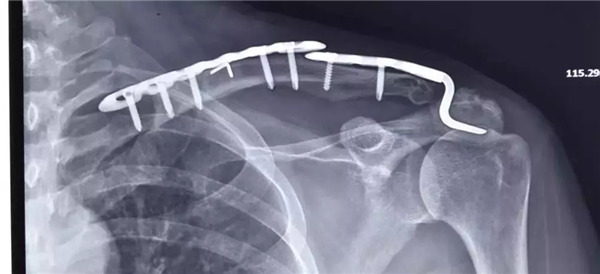

術(shù)后拍片

經(jīng)患者與家屬同意后,羅軍主任手術(shù)團(tuán)隊(duì)成功為患者實(shí)施了左肩鎖關(guān)節(jié)復(fù)位Y型Endobutton固定系統(tǒng)固定術(shù)。手術(shù)只用50分鐘時(shí)間。術(shù)后X片復(fù)查顯示肩鎖關(guān)節(jié)脫位完全復(fù)位,術(shù)后第二天楊女士在康復(fù)醫(yī)師指導(dǎo)下開(kāi)始進(jìn)行左肩關(guān)節(jié)功能鍛煉,楊女士左肩部疼痛明顯減輕,左肩關(guān)節(jié)可抬起、前舉,功能較術(shù)前明顯改善,楊女士大約再經(jīng)過(guò)3-4周康復(fù)訓(xùn)練左肩關(guān)節(jié)功能可恢復(fù)正常。